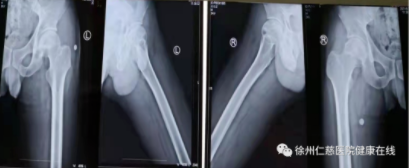

34岁男性患者,因“双髋关节疼痛伴活动受限33天”入院。双髓关节正位片示:双侧股骨头稍变扁,密度不均,双侧髋骨质增生改变、密度增高,髋关节间隙稍窄、不等宽,诊断双侧股骨头缺血性坏死(II期) 。

治疗前

治疗2个月后

采用钻孔减压+体外冲击波+激光磁治疗综合治疗后,患者双髋疼痛消失,关节活动正常。